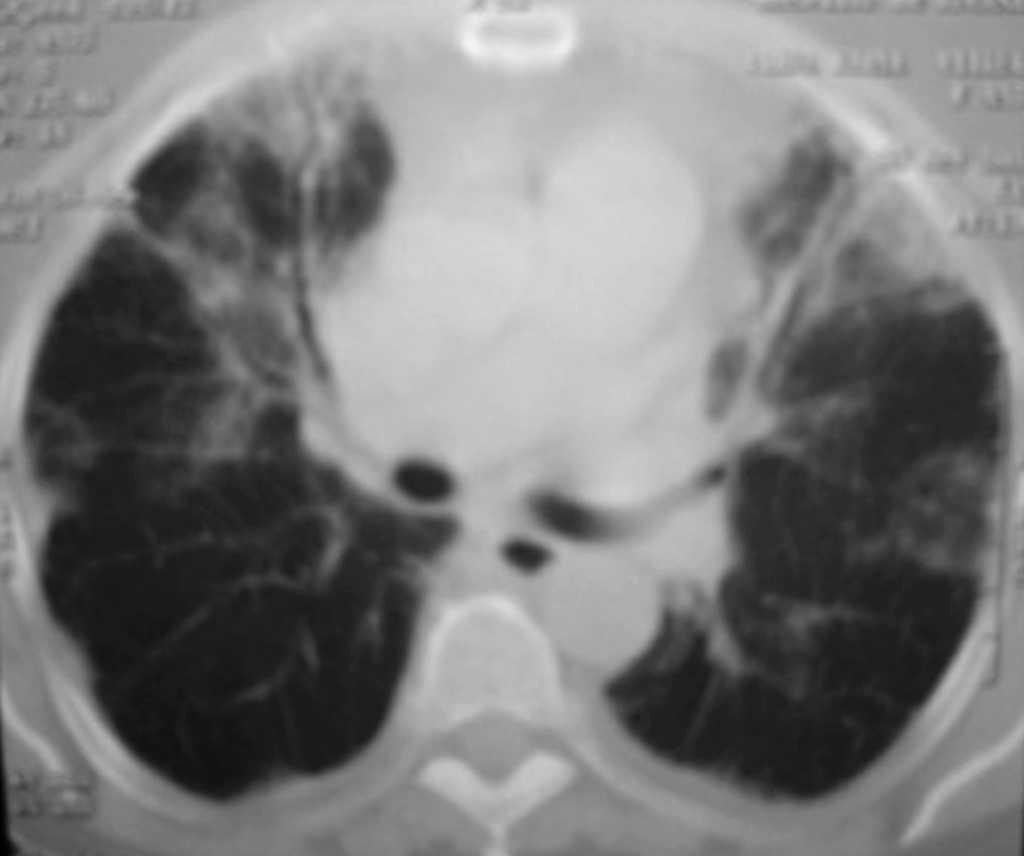

da de disnea que progresivamente se había hecho a medianos esfuerzos. La paciente había llevado tratamiento con antitusígenos y antibióticos a pesar de lo cual había empeorado. Se encontraba afebril. Tenía una tensión arterial de 140/70 mmHg y una frecuencia cardíaca de 70 lpm. En el momento de la exploración la paciente se encuentra eupneica en reposo, normohidratada, sin cianosis central ni periférica. No se evidencia ingurgitación yugular ni adenopatías, ni soplos carotídeos. En la auscultación cardíaca hay ruidos rítmicos sin soplos ni roce pericárdico. En la auscultación pulmonar se observan crepitantes en campos medios, sobre todo derecho. El abdomen no es doloroso, no presenta megalias y el peristaltismo está conservado. Las extremidades inferiores no muestran edemas ni signos de insuficiencia venosa, con pulsos pedios simétricos. En las pruebas complementarias destaca en el hemograma neutrofilia sin leucocitosis. La bioquímica y la hemostasia son normales. El electrocardiograma muestra ritmo sinusal sin crecimiento de cavidades. Gasometría: pH: 7,46; pCO2: 32,8; pO2: 55,5; bicarbonato: 23,5; saturación O2: 90,7%. La radiografía de tórax muestra patrón intersticial bilateral (fig. 1); no hay imágenes de condensación. La paciente ingresó en el servicio de Medicina Interna para estudio de insuficiencia respiratoria y patrón intersticial pulmonar. La tomografía axial computarizada evidenciaba la existencia de múltiples zonas de consolidación parenquimatosa de distribución periférica acompañado de engrosamiento y dilatación de la pared bronquial (fig. 2). La espirometría mostraba un déficit restrictivo de carácter moderado-severo y las pruebas reumatológicas solicitadas fueron normales a excepción del factor reumatoide (168) y la proteína C reactiva (37,1). Se inició tratamiento corticoideo a dosis elevadas y la paciente mejoró espectacularmente tanto clínica como radiológicamente.

Figura 2. Tomografía axial computarizada torácica.